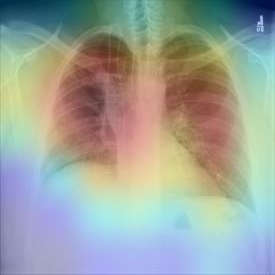

The COVID-19 disease was first discovered in Wuhan, China, and spread quickly worldwide. After the COVID-19 pandemic, many researchers have begun to identify a way to diagnose the COVID-19 using chest X-ray images. The early diagnosis of this disease can significantly impact the treatment process. In this article, we propose a new technique that is faster and more accurate than the other methods reported in the literature. The proposed method uses a combination of DenseNet169 and MobileNet Deep Neural Networks to extract the features of the patient's X-ray images. Using the univariate feature selection algorithm, we refined the features for the most important ones. Then we applied the selected features as input to the LightGBM (Light Gradient Boosting Machine) algorithm for classification. To assess the effectiveness of the proposed method, the ChestX-ray8 dataset, which includes 1125 X-ray images of the patient's chest, was used. The proposed method achieved 98.54% and 91.11% accuracies in the two-class (COVID-19, Healthy) and multi-class (COVID-19, Healthy, Pneumonia) classification problems, respectively. It is worth mentioning that we have used Gradient-weighted Class Activation Mapping (Grad-CAM) for further analysis.